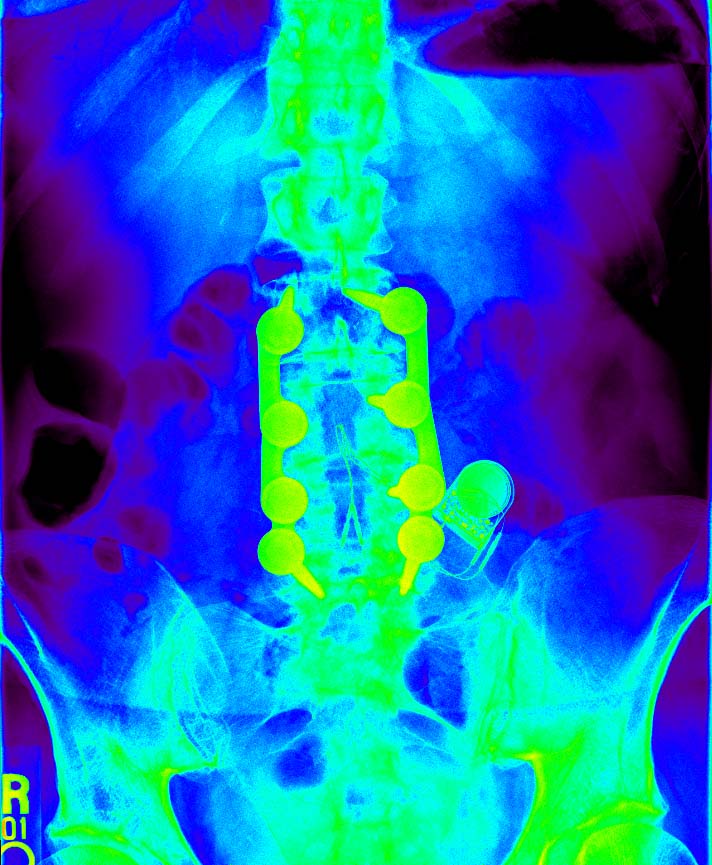

The Wonders of Modern Medicine and Computer Graphics

check out the battery...it's no longer doing anything, but my ashes will be toxic waste.

and the side view...